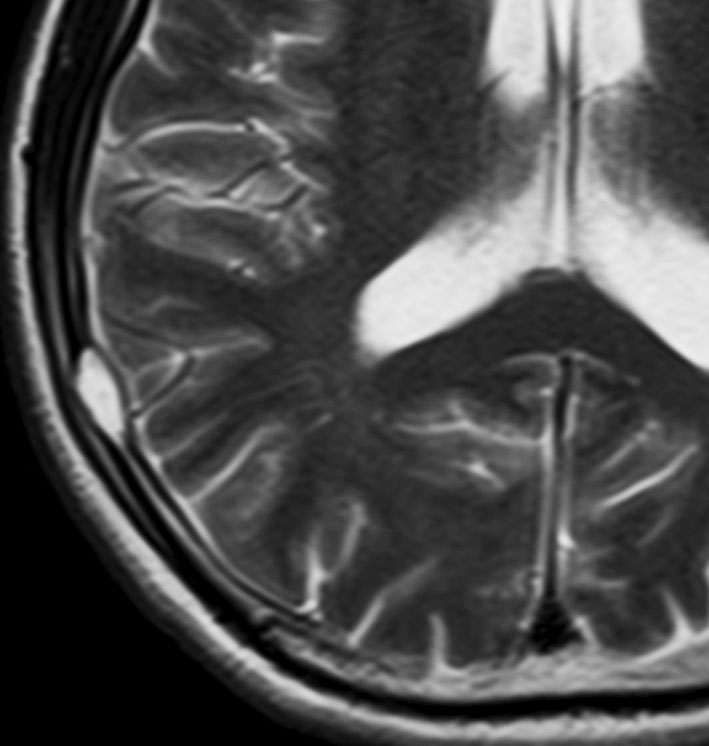

生検術だけして経過を見ると骨欠損が修復される

中年の女性の頭頂部に発生したものです。症状は頭皮の膨隆でした。生検術でLCHと診断して,しばらく経過を見たら自然退縮しました。

左は発症時,右は2年後のCTです。骨欠損部は自然修復されています。LCHの小さな骨欠損は頭蓋形成しなくても良いです。